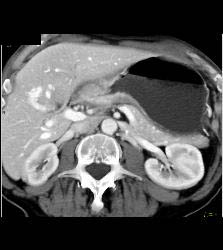

Antral Carcinoma